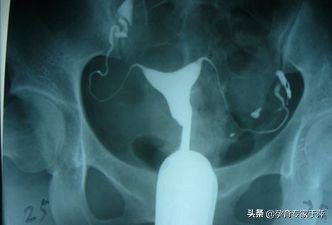

问:什么是子宫输卵管造影?

答:将造影剂注射到子宫腔内,造影剂可以经过输卵管进入盆腹腔内,在X线下可以清晰地看到子宫腔及两侧的输卵管的形态,是否通畅,是堵塞、黏连还是通而不畅,病灶的位置等都能清晰的看到。子宫输卵管造影术是输卵管通畅度的一线筛查手段。